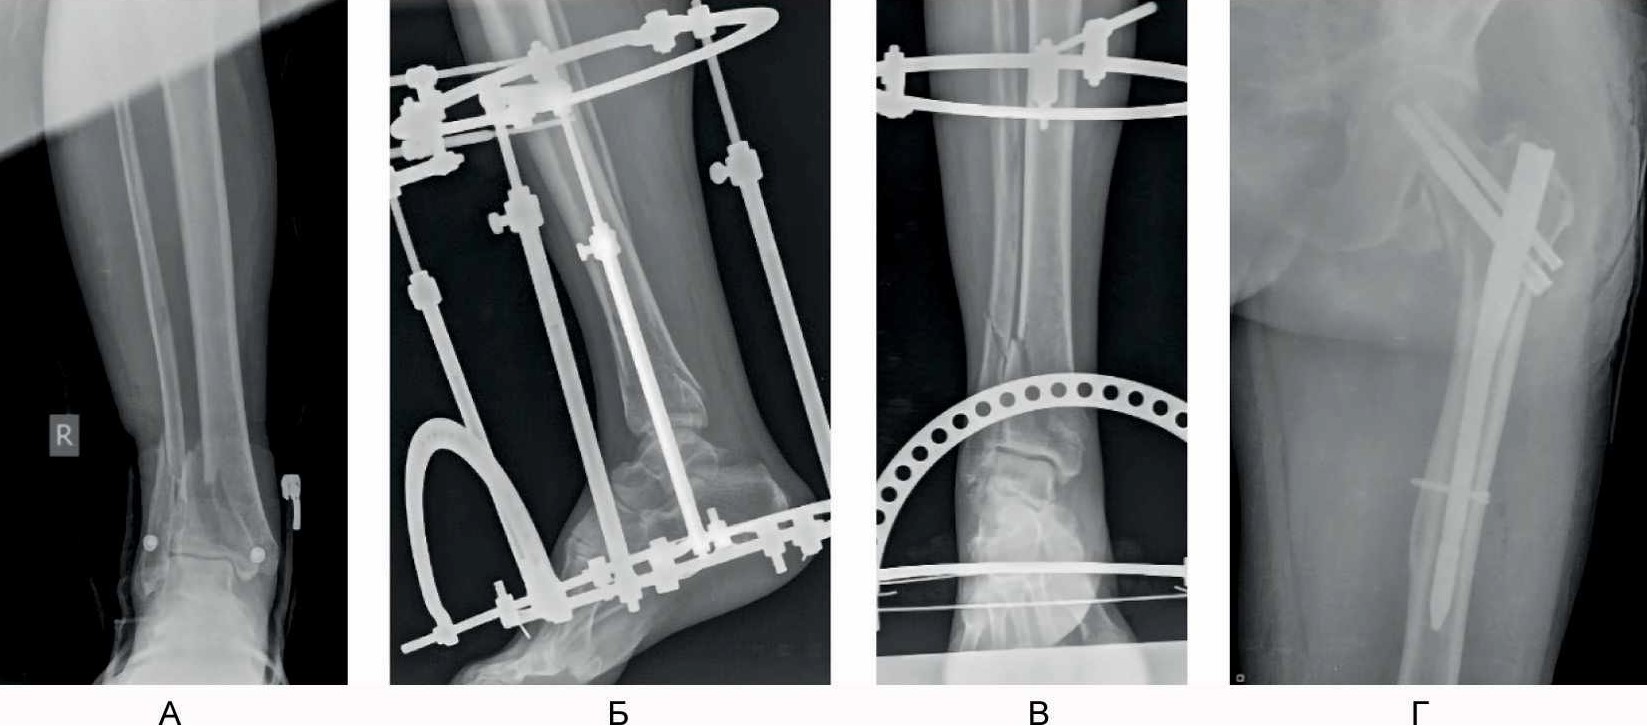

С учетом стабильного состояния пациента, в соответствии с протоколом лечения множественной и сочетанной травмы, пациент доставлен в операционную. Выполнена операция: закрытая репозиция, малоинвазивный остеосинтез левой бедренной кости проксимальным бедренным стержнем, внеочаговый остеосинтез правой голени аппаратом наружной фиксации с умеренной тракцией (рис. 1), первичная хирургическая обработка раны лба.

Рис. 1. Рентгенограммы пациента Б, 66 лет, в день поступления. А – первичная рентгенограмма голени и голеностопного сустава в прямой проекции; Б, В – первичная закрытая репозиция аппаратом наружной фиксации; Г – результат интрамедуллярного остеосинтеза перелома проксимального отдела бедренной кости.

Послеоперационный период протекал без особенностей. Показаний к оперативному лечению перелома орбиты не выявлено. Пациент дообследован, выполнена компьютерная томография дистального отдела голени для окончательной верификации типа перелома и проведения предоперационного планирования (рис. 2).